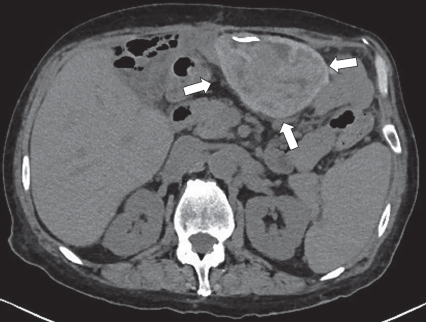

Figura 1 Tomografía de abdomen simple en plano axial